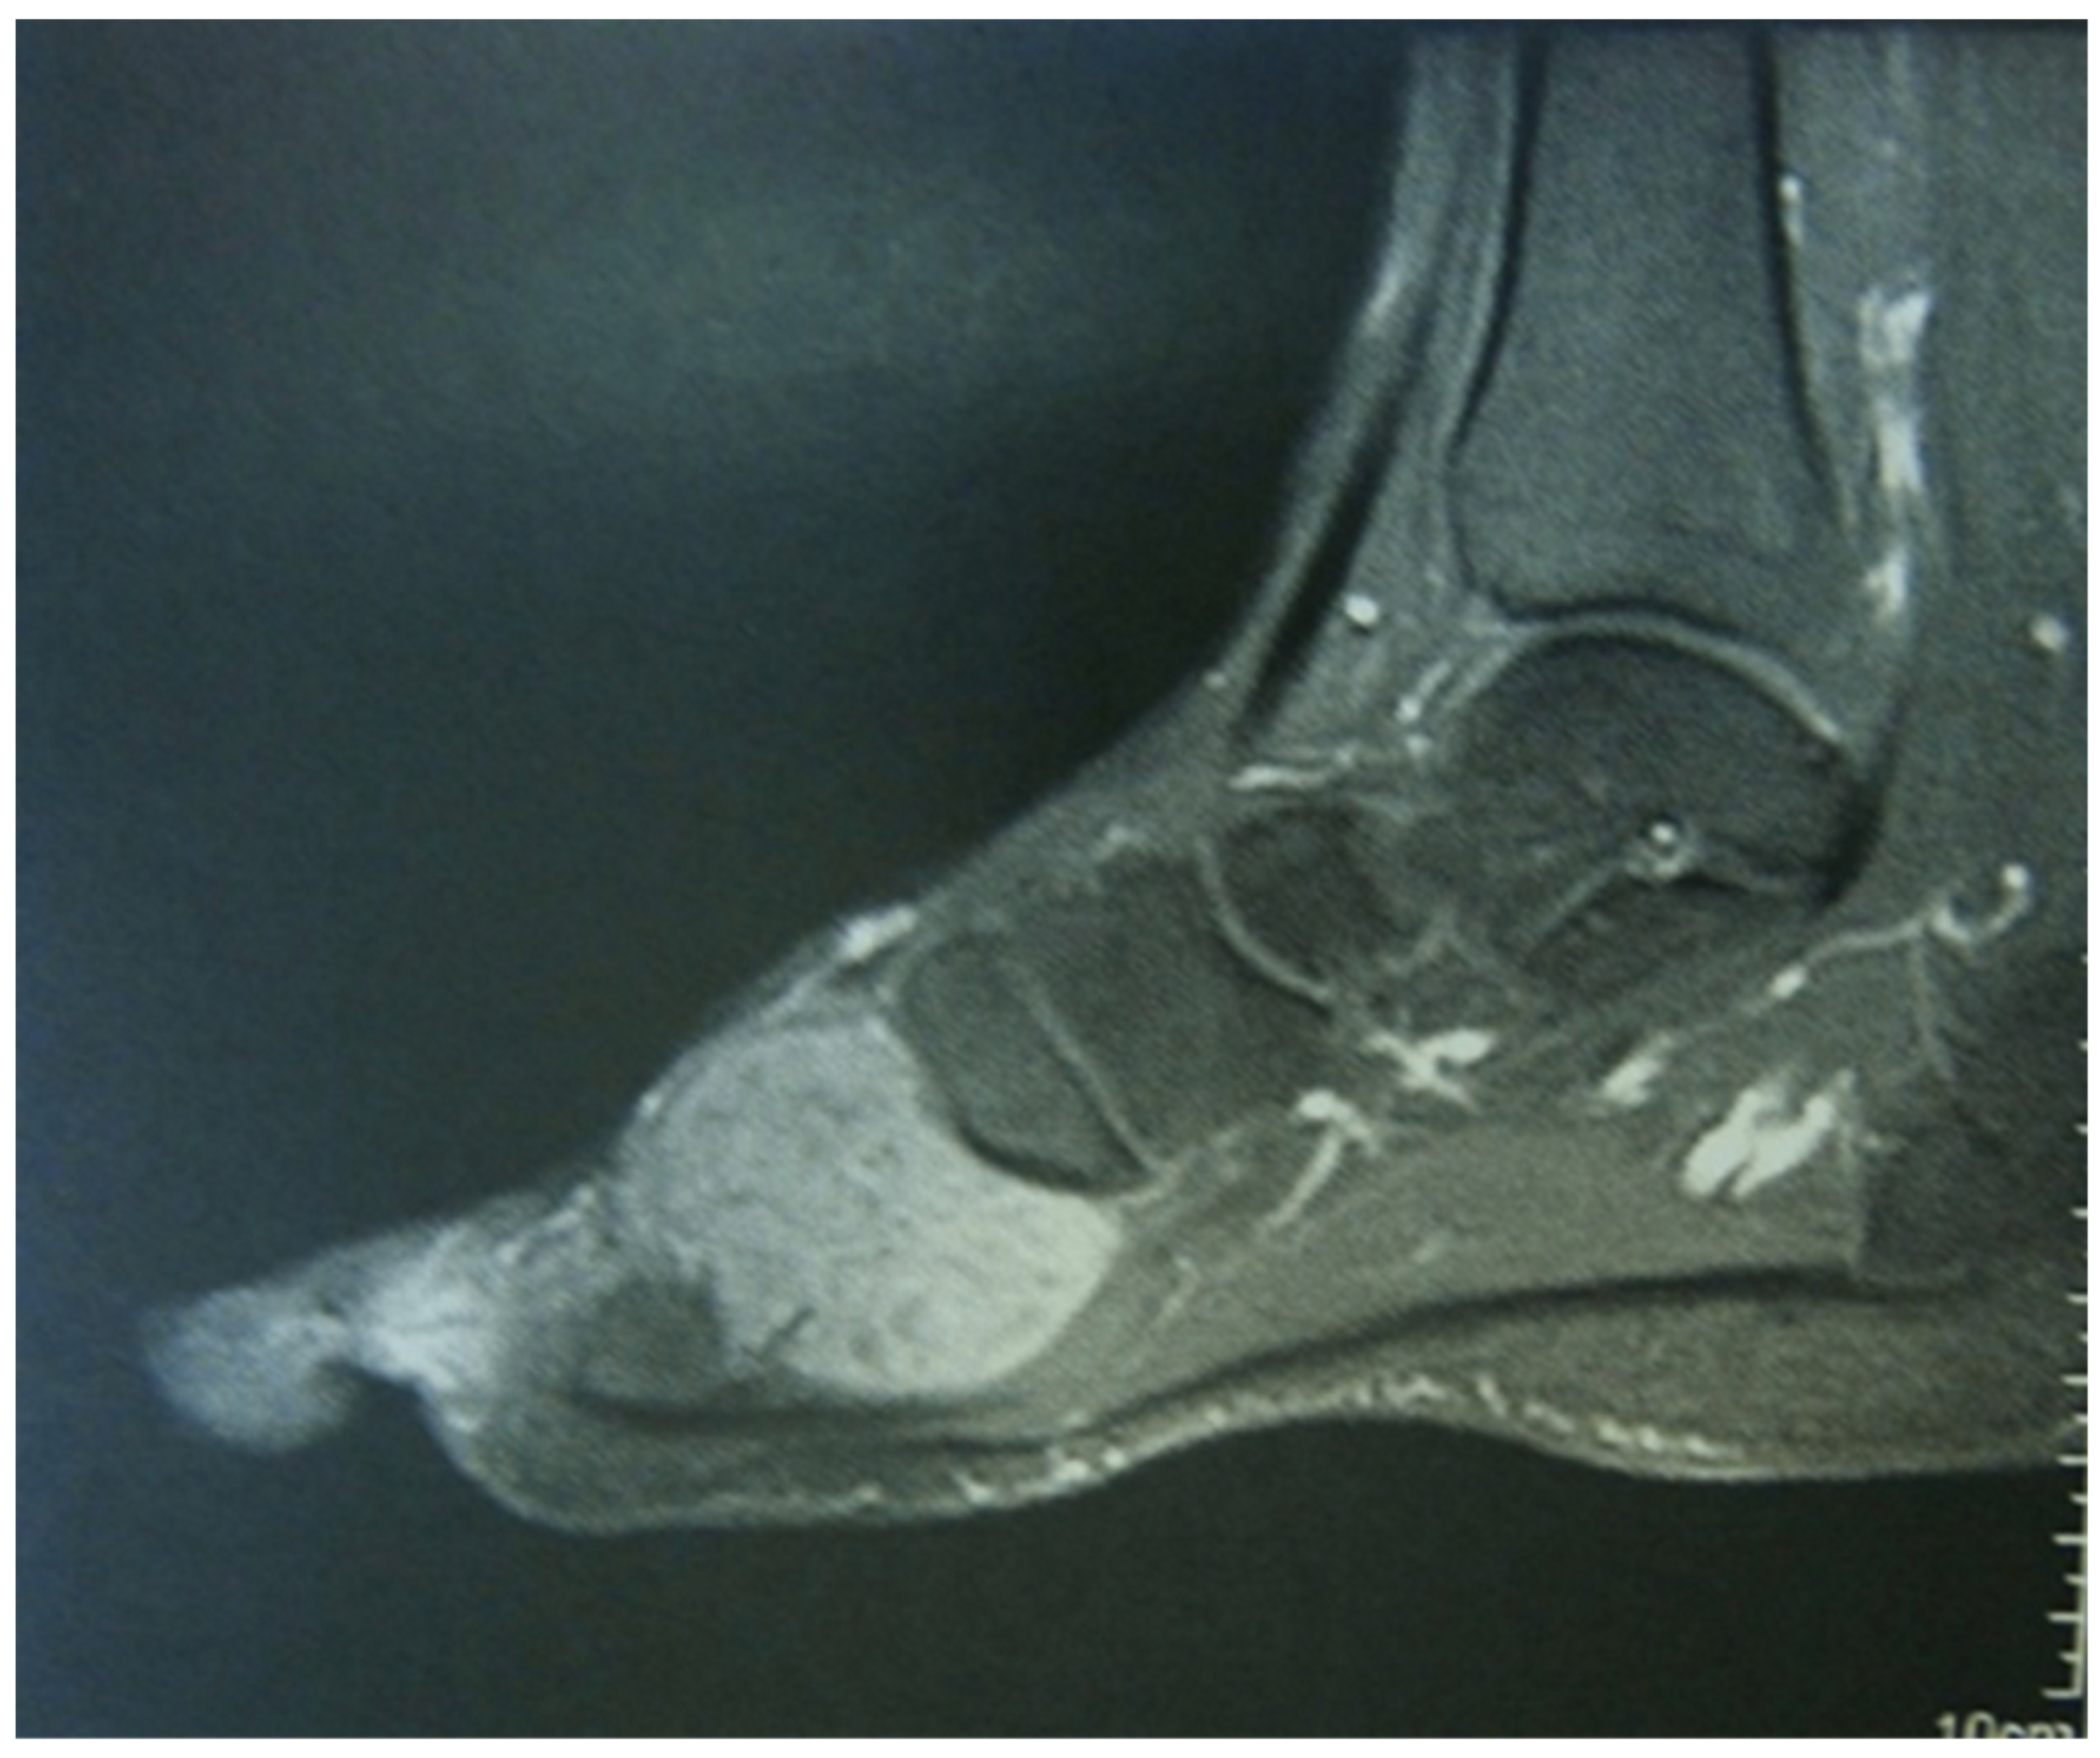

4. Imaging